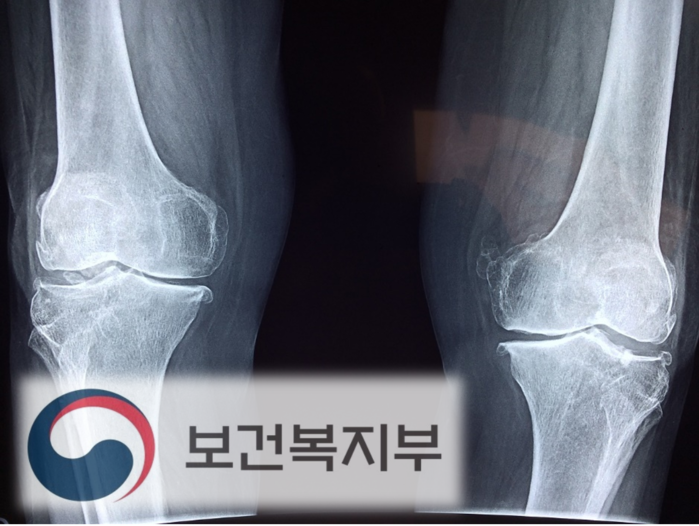

[로컬세계 최종욱 기자]앞으로 60세 이상 어르신도 무릎관절증 치료 지원금을 받을 수 있게된다. 지원규모도 확대돼 한쪽 무릎 당 최대 120만원까지 지원된다.

무릎관절증 의료비는 양쪽 무릎을 기준으로 식대·마취료 등 급여 항목 본인부담금 19만원에 MRI·초음파 등 비급여 항목 부담금이 더해져 340만9000원이 나올 만큼 몸이 불편해도 수술을 꺼리게 되는 이유가 되기도 했다.

지난해에는 한쪽 무릎 당 평균 47만9000이었던 지원금을 이제는 최대 120만원까지 지원한다.

또 지원대상 연령은 65세 이상에서 60세 이상으로 낮췄다. 실제로 2017년 무릎관절증 전체 입원환자 11만6813명 중 65세 미만은 42.4%를 차지할 만큼 많은 것으로 나타났다.